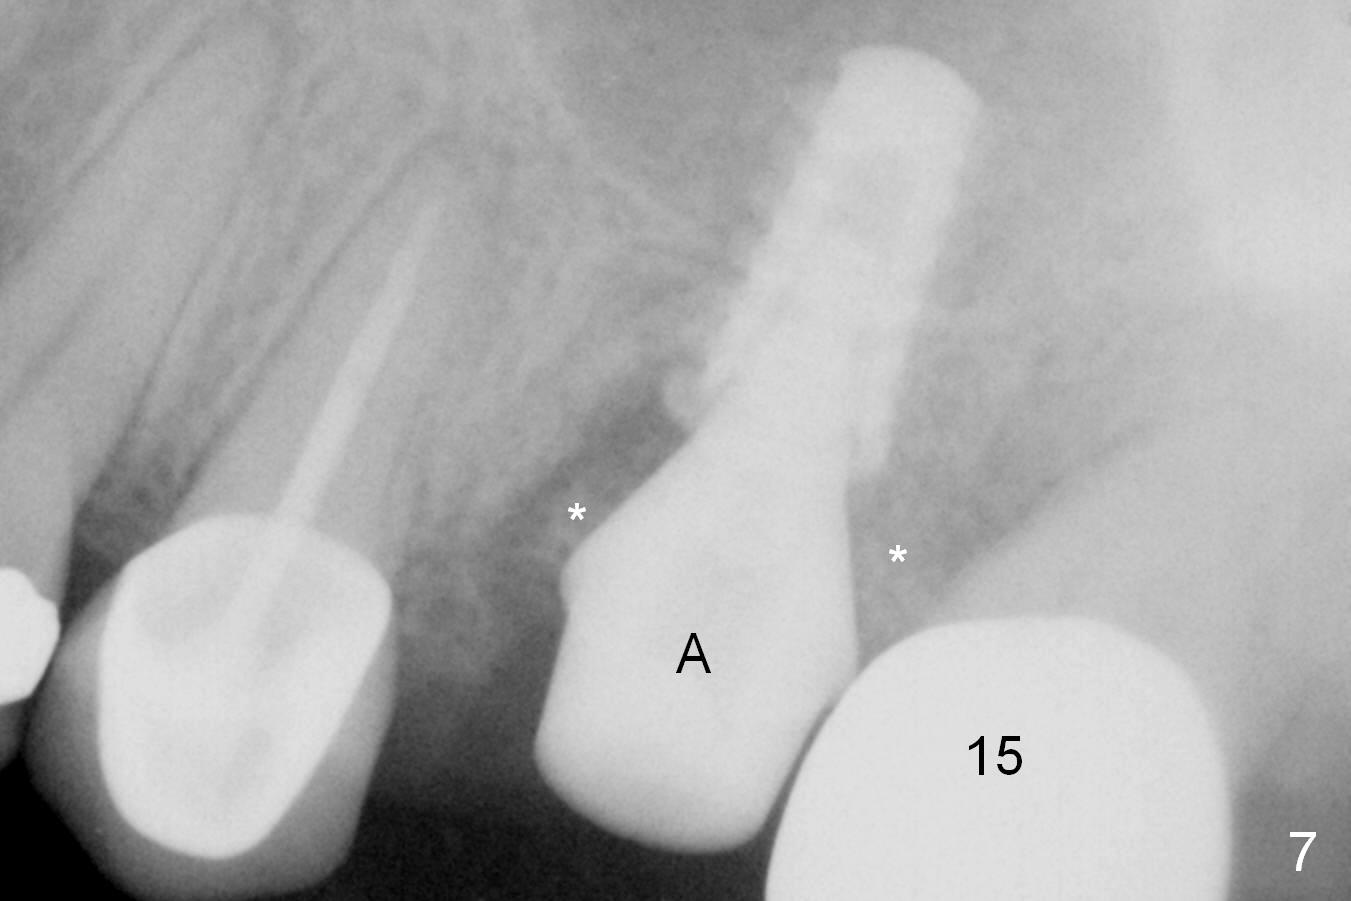

When the affected tooth is extracted, the suitable site for implantation is the large palatal socket.  Osteotomy is initiated with Magic Expander 3.0 mm (red circle or arrow in Fig.1 (occlusal view), 2 ((coronal section)) as buccally as possible, since the palatal plate (P) is shorter than the buccal one (B in Fig.2).  The sinus floor turns out to be thin.  When the osteotomy at the sinus floor increases equivalent to the apical diameter of a 5 mm implant, a 5x9 mm dummy one is placed (Fig.6).  There are two errors, one recognized immediately, the other not.  The implant is placed too apically, but the sinus membrane remains intact.  After placing 2 pieces of PRF membrane and allograft (.5-1.0 mm), a larger implant is placed (5.5x9 mm IBS) is placed at the palatal crestal level (Fig.4) with minimal stability.  When a 6.5x4(4) mm abutment is being placed, it turns the underlying implant so that the latter is placed more apically (Fig.5,7).  Ideally, a much larger implant should have been chosen (6.0 or 6.5 mm, Fig.3 green circle).  In the future, tap drills should be used prior to implantation if the sinus floor is thin.  The abutment in this case (Fig.7 A) is close to the tooth #15.  The latter is the 2nd error not recognized earlier (Fig.6).  The trajectory should have been corrected when a more definitive implant is being placed (from black line to red line).

The patient is doing well 9 days postop.  The immediate provisional is loose and over-sized.  It is removed for trimming and reline; the socket and bone graft (Fig.8 *) are healing.  It appears that an angled abutment is required next time of provisional revision.  When an angled abutment is being placed 23 days postop (Fig.9), it appears to wiggle the implant due to its long leverage.  Instead a healing abutment is placed.  The implant is unstable 4.5 months postop with seemingly excessive bone-implant gap (Fig.10 <).  The 5.5x9 mm implant is removed.  A 5x17 mm tap is used to change the trajectory and sinus lift, followed by 6x17 one (Fig.11).  Finally a 6x14 mm tissue-level implant is placed with insertion torque > 50 Ncm (Fig.12; vs. <20 Ncm (Fig.7,10)) and improved trajectory.  An immediate provisional is fabricated to prevent the mesial drifting of the tooth #15 (Fig.13 P (*: occlusal clearance)).  By using the taps and placing the longer implant, the sinus lift is more obvious (compare Fig.10 and 12 (*)).  Sinus lift remains evident 3.5 months postop (Fig.14) with apparently osteointegration (Fig.15).